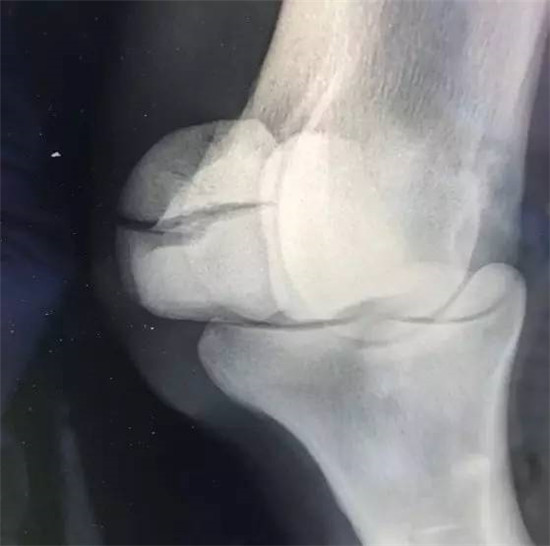

▲“巨鹰拍翼”近端籽骨骨折X光下摄片,图片来源Racing UK。

▲X光拍摄马匹球节部位

▲“巨鹰拍翼”近端籽骨骨折斜位图,可发现近端籽骨明显裂开。图片来源Racing UK。